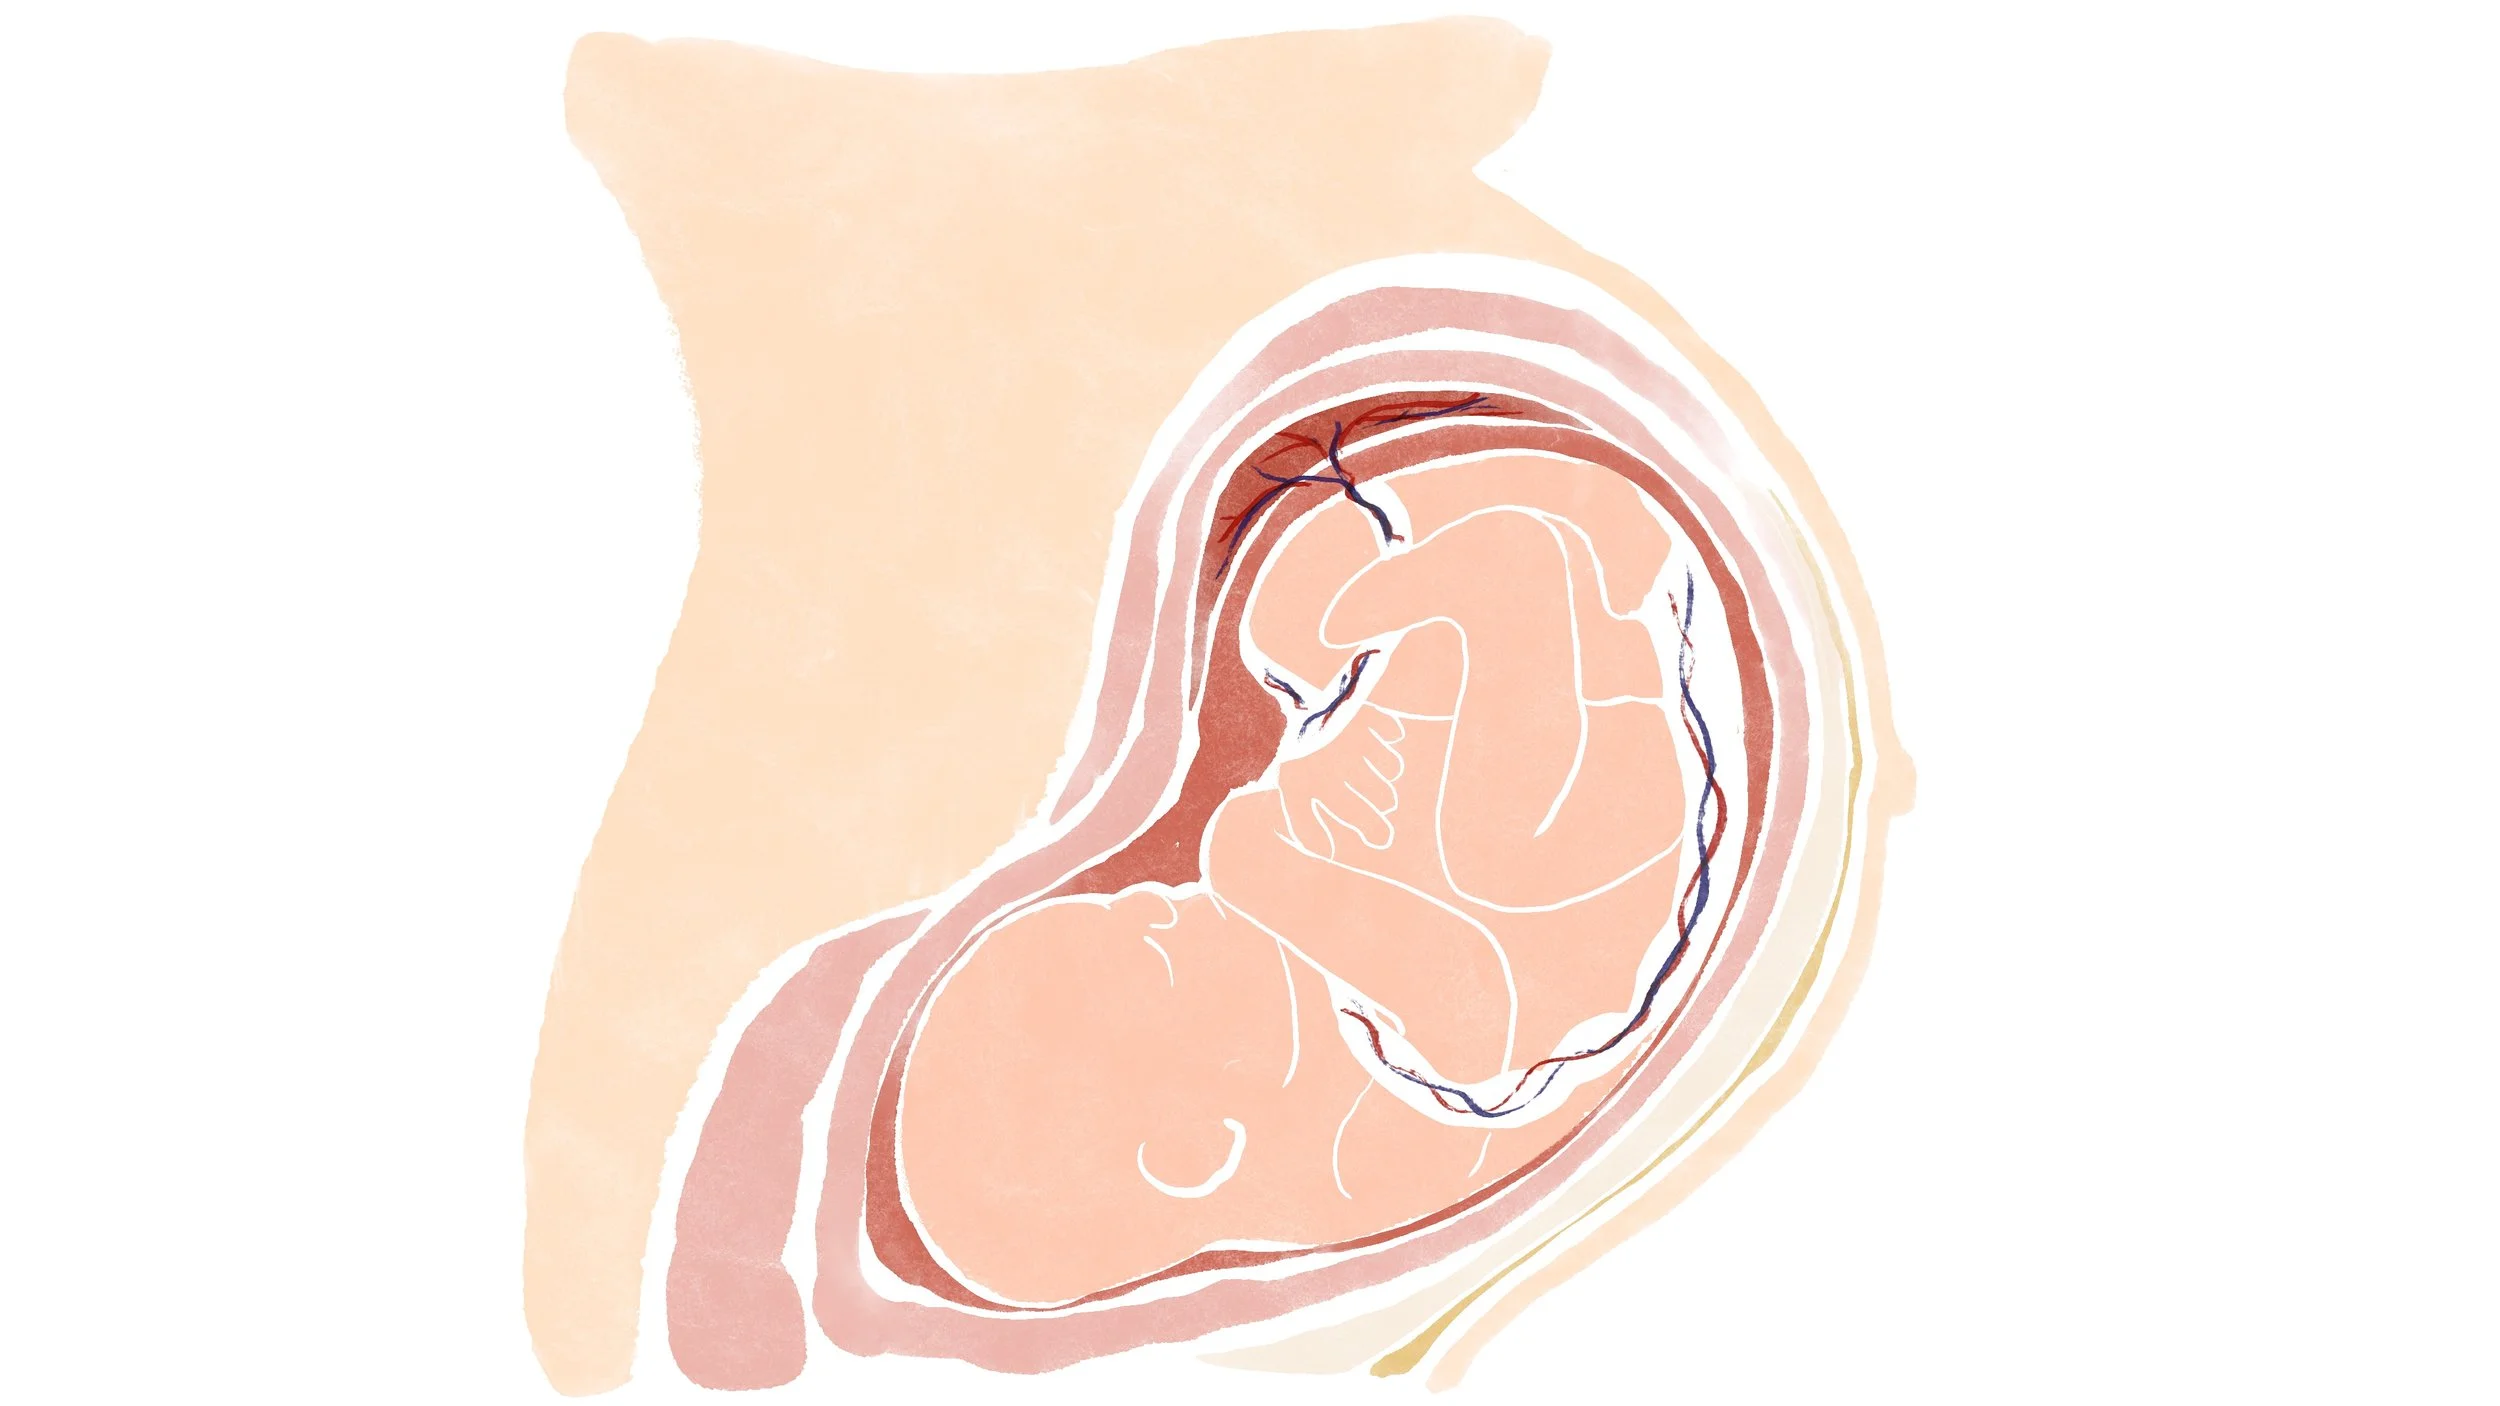

Fetus in womb

Fetus in womb

Fetus in womb